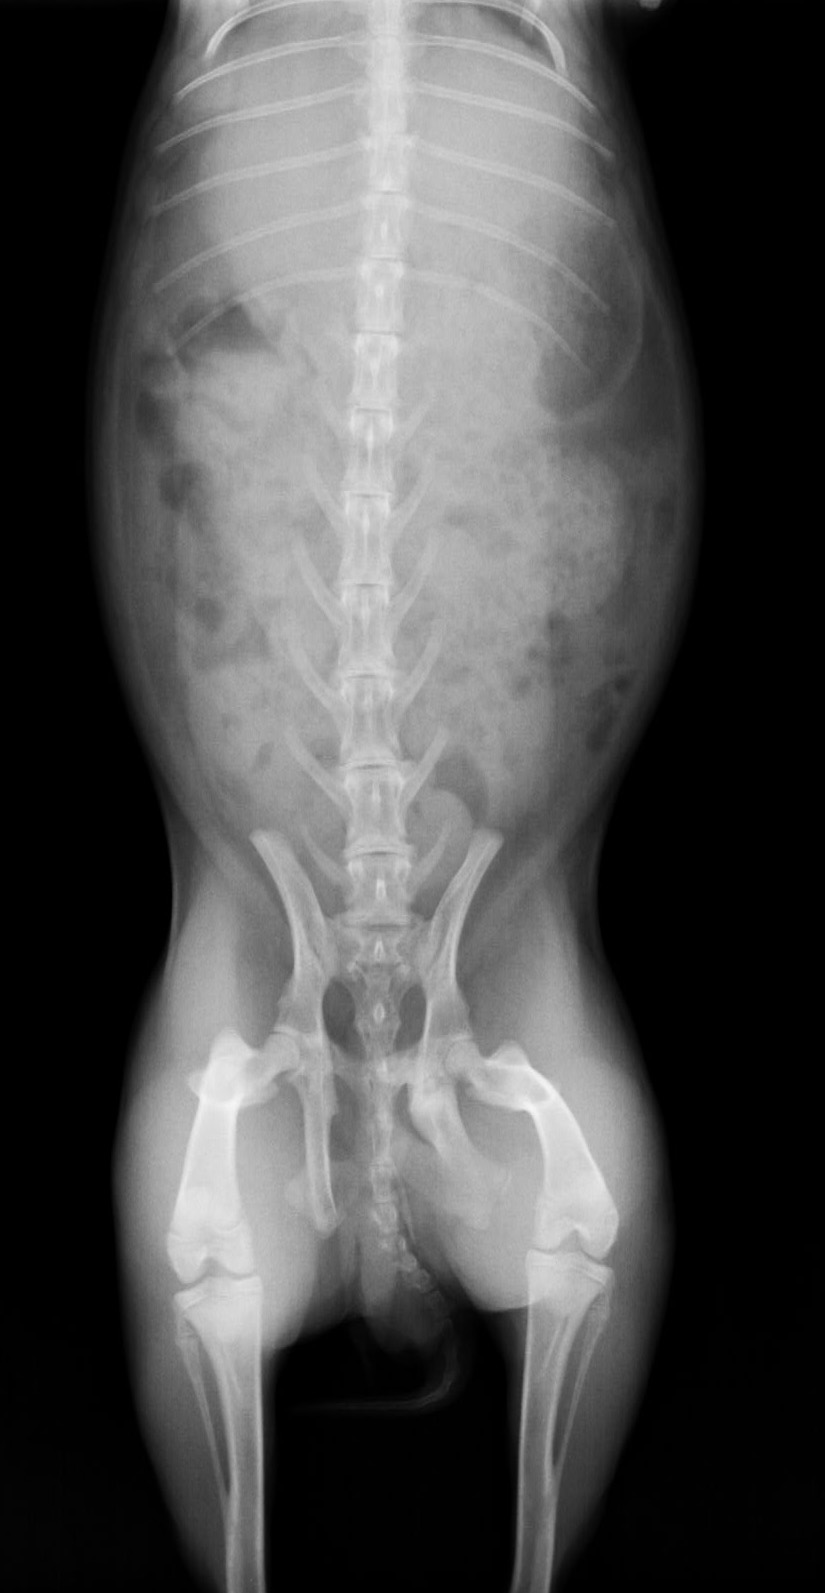

この症例は骨盤を骨折しており、左骨盤腸骨の股関節の下が骨折しています。また恥骨結合側も骨折してる。

骨端線がはっきりしているので成長期のウサギということがわかります。

比較的変異が少ない場合手術固定するよりもそのまま安静にする方が結果としてよい場合があります。

他の合併症(出血や内臓の障害)に注意します。

骨折の場所が内側に入り込んでいるので完治するまでにもう少し内側に入りこむと思われます。

その場合便秘、排尿障害、雌の場合は出産困難などが考えられます。